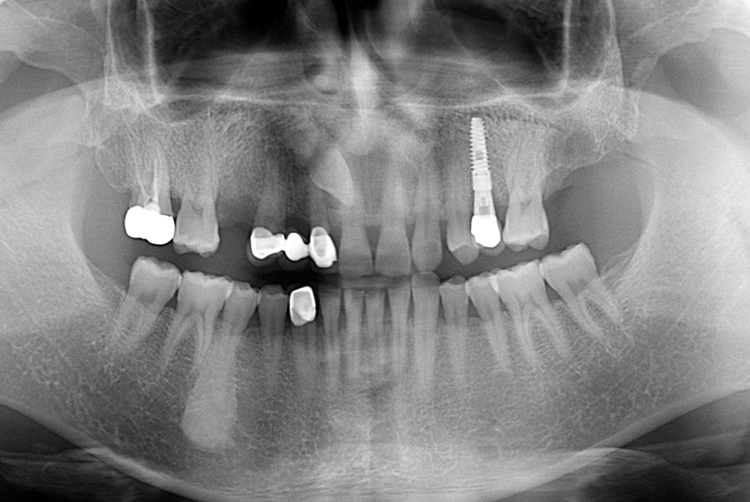

[임플란트] 어금니 임플란트

치료후 : 2019-08-30

세종치과는 많은 환자와 다양한 케이스를 바탕으로

항상 편안한 임플란트 수술을 제공하고자 노력하고,

오래동안 튼튼히 쓸 수 있는 임플란트 수술을 가장 큰 목표로 삼고 있습니다.